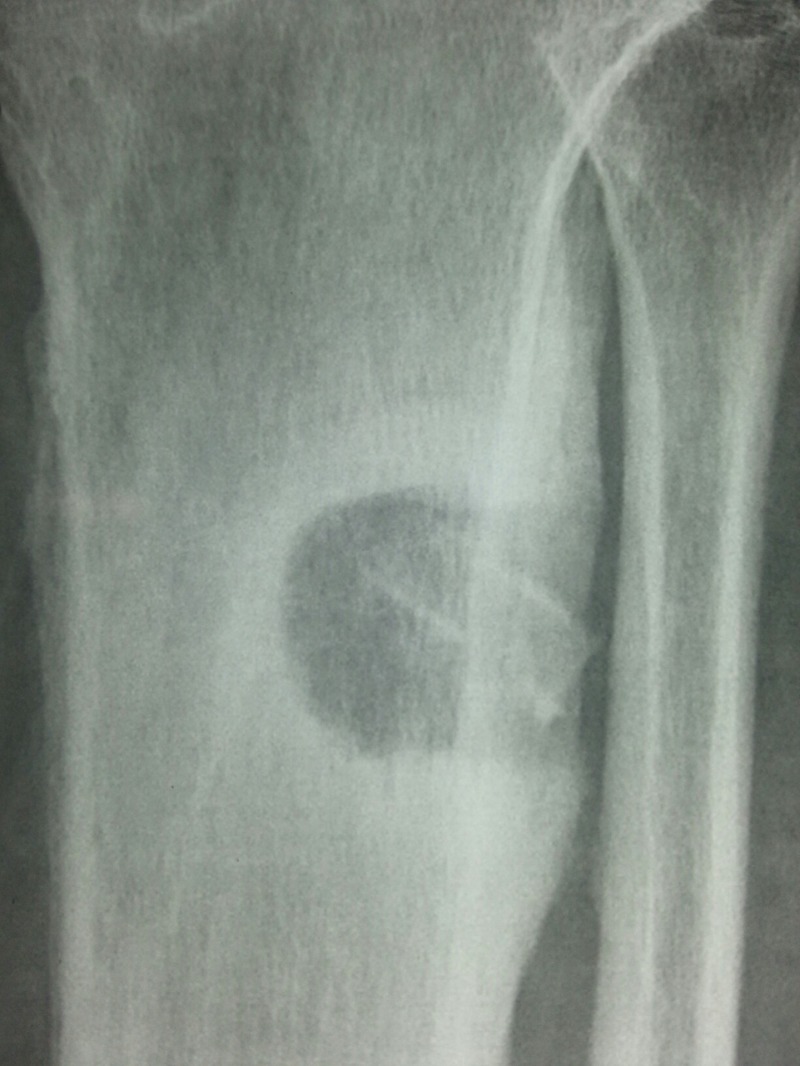

Figure 3.

Lateral view of the leg showing ring sequestrum with surrounding dense sclerosis in the upper tibia.